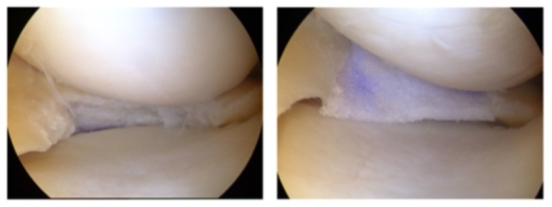

Meniskustherapie

In Deutschland werden jährlich 420.000 Meniskusoperationen durchgeführt. In 50 % der Fälle handelt es sich um akute, unfallbedingte Verletzungen bei überwiegend jüngeren Patienten. Obwohl es wissenschaftlich erwiesen ist, dass eine Meniskusentfernung zwangsläufig mit einer Arthrose des Kniegelenkes in einem Zeitraum von 10-15 Jahren vergesellschaftet ist, werden lediglich in weniger als 10 % der Fälle meniskuserhaltende Operationen durchgeführt.

Um diese schwerwiegenden und irreparablen Folgeschäden zu vermeiden, ist es unser Ziel, so häufig wie möglich eine rekonstruktive Meniskuschirurgie durchzuführen und damit den Meniskus zu erhalten. Ist dies aufgrund der Schwere der Verletzung nicht möglich, führen wir an unserer Klinik bei speziellen Indikationen auch Meniskustransplantationen durch.